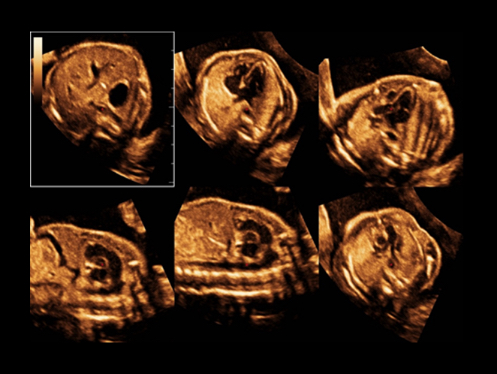

DC-80A con X-Insight mette a disposizione strumenti di una intelligenza eccezionale specifici per la cura della donna, dalla fertilit├Ā allo screening prenatale, e al post partum.

Immagini cliniche